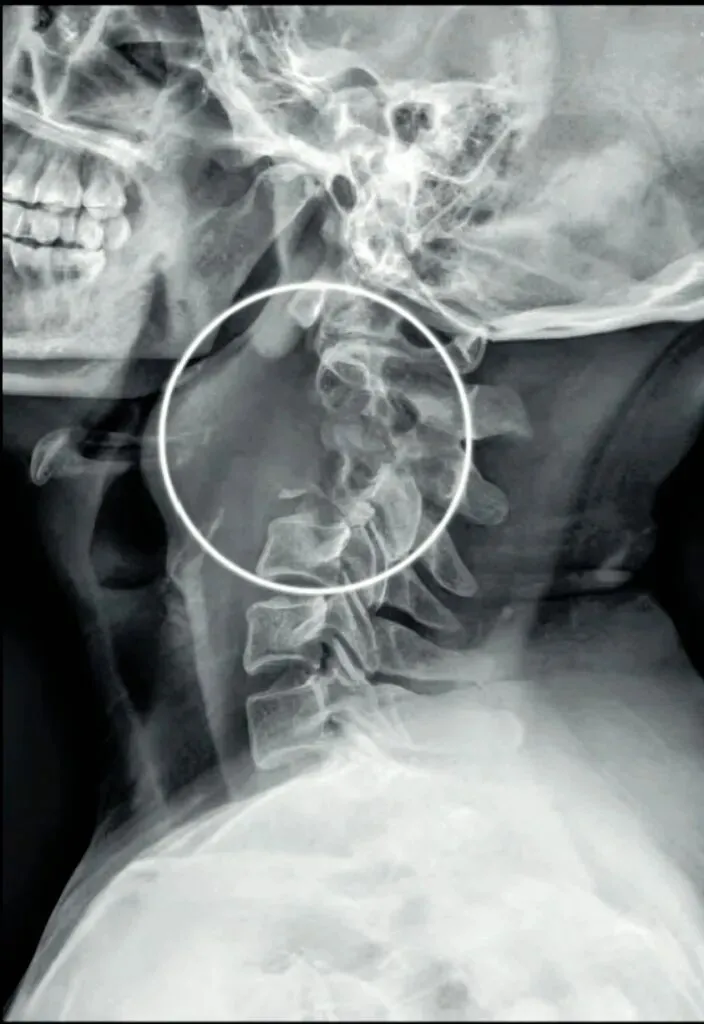

二弓指的是颈椎生理曲度,在颈椎侧位X线片中,正常生理状态下呈现向前凸出的弧形曲线,呈半C型前凸类似弓形,是人体脊柱生理曲度的重要组成部分。颈椎曲度变化能够反映颈椎整体功能的变化。

常见的颈椎曲度改变有曲度变直和曲度反曲。

颈椎生理曲度测量的方法多种多样,其中应用最广泛的测量方法是Borden法。从齿状突后上缘开始向下将每个椎体后缘相连成为一条弧线,然后从齿状突后上缘至C7椎体后下缘作一直线测量,两条线间最宽处的垂直横交线的距离即为颈椎生理曲度深度。

正常时,最宽处在C4椎体水平正常为12毫米,正负5毫米,小于7毫米为生理曲度变直,大于17毫米为生理曲度过度前屈,小于零时为生理曲度反曲。